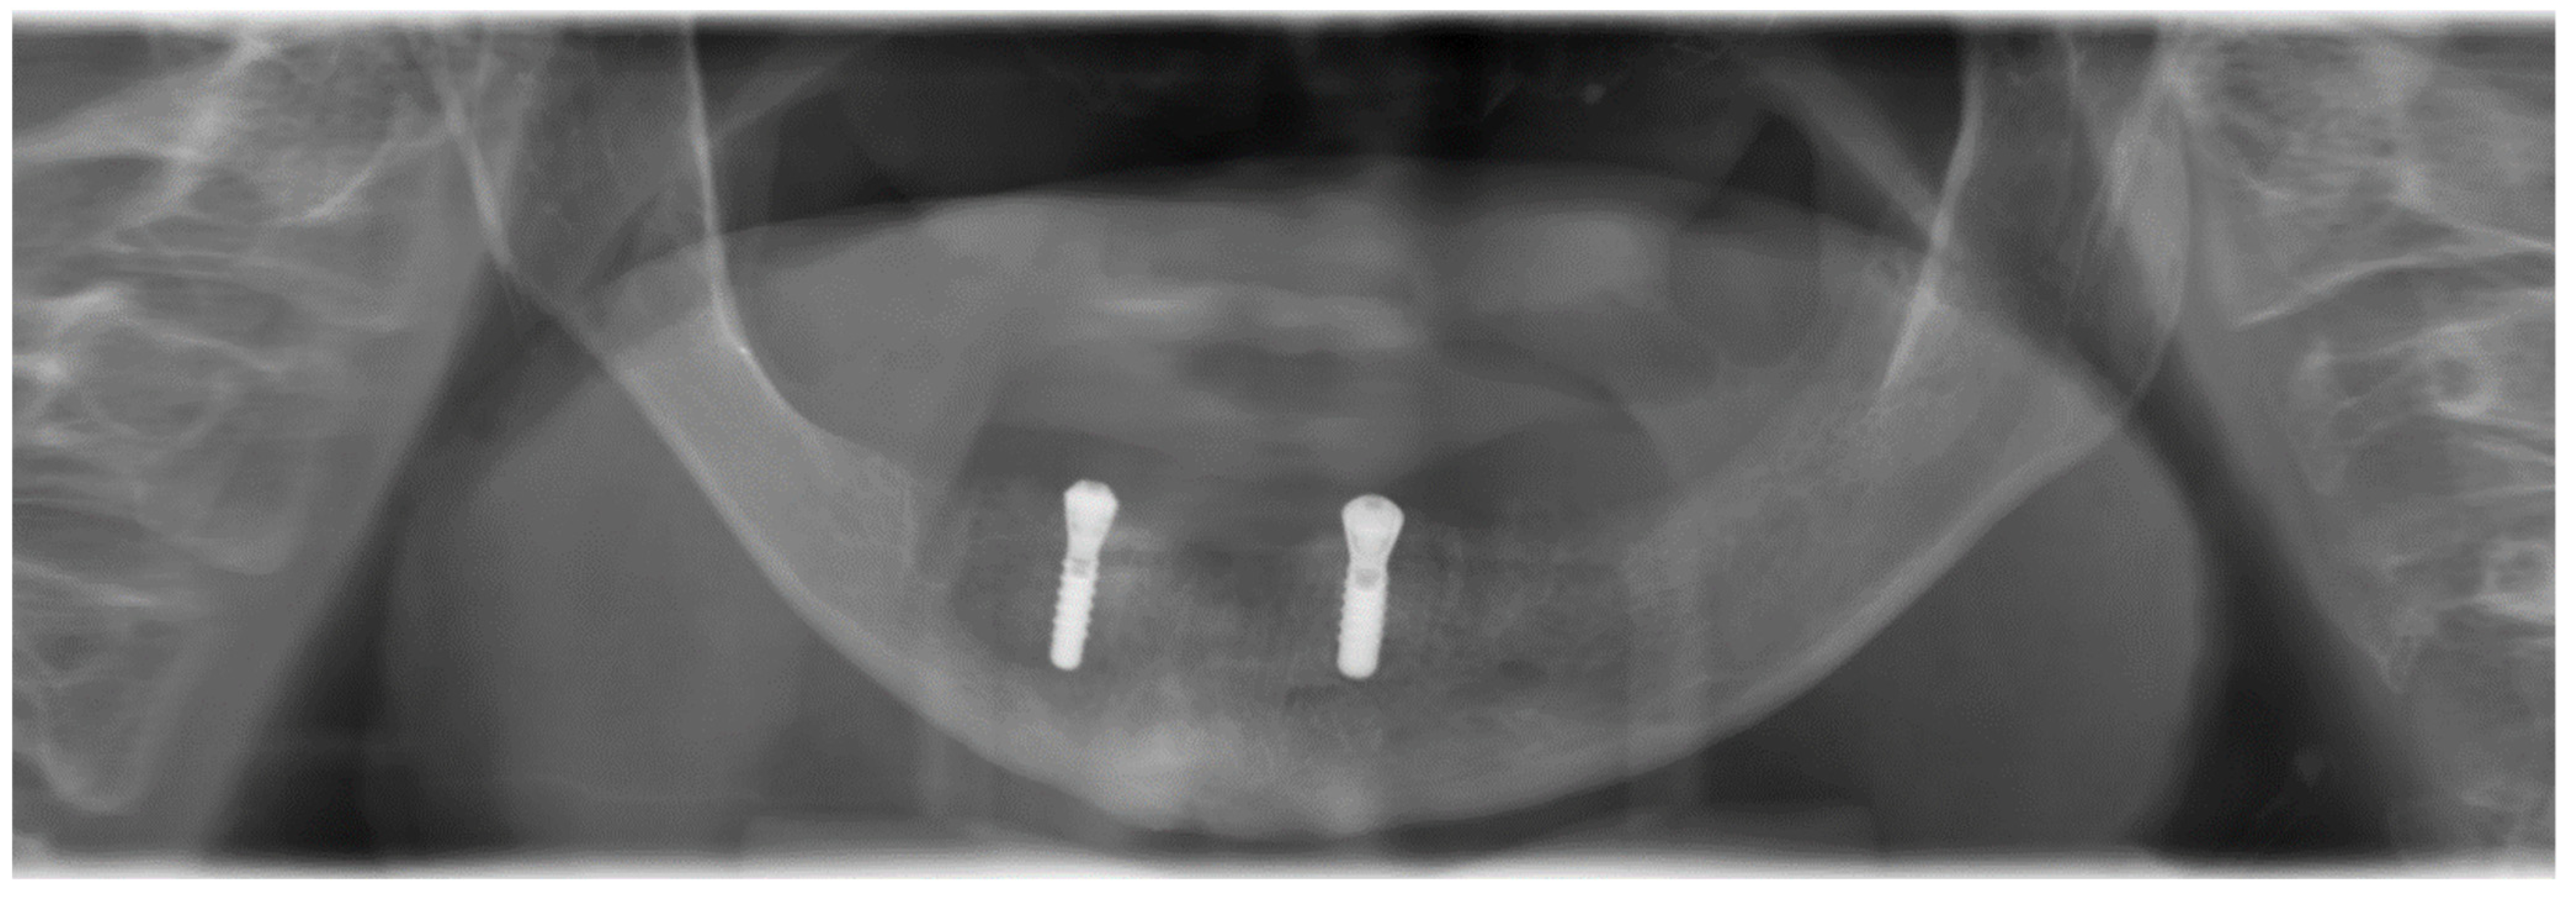

2. Case Report